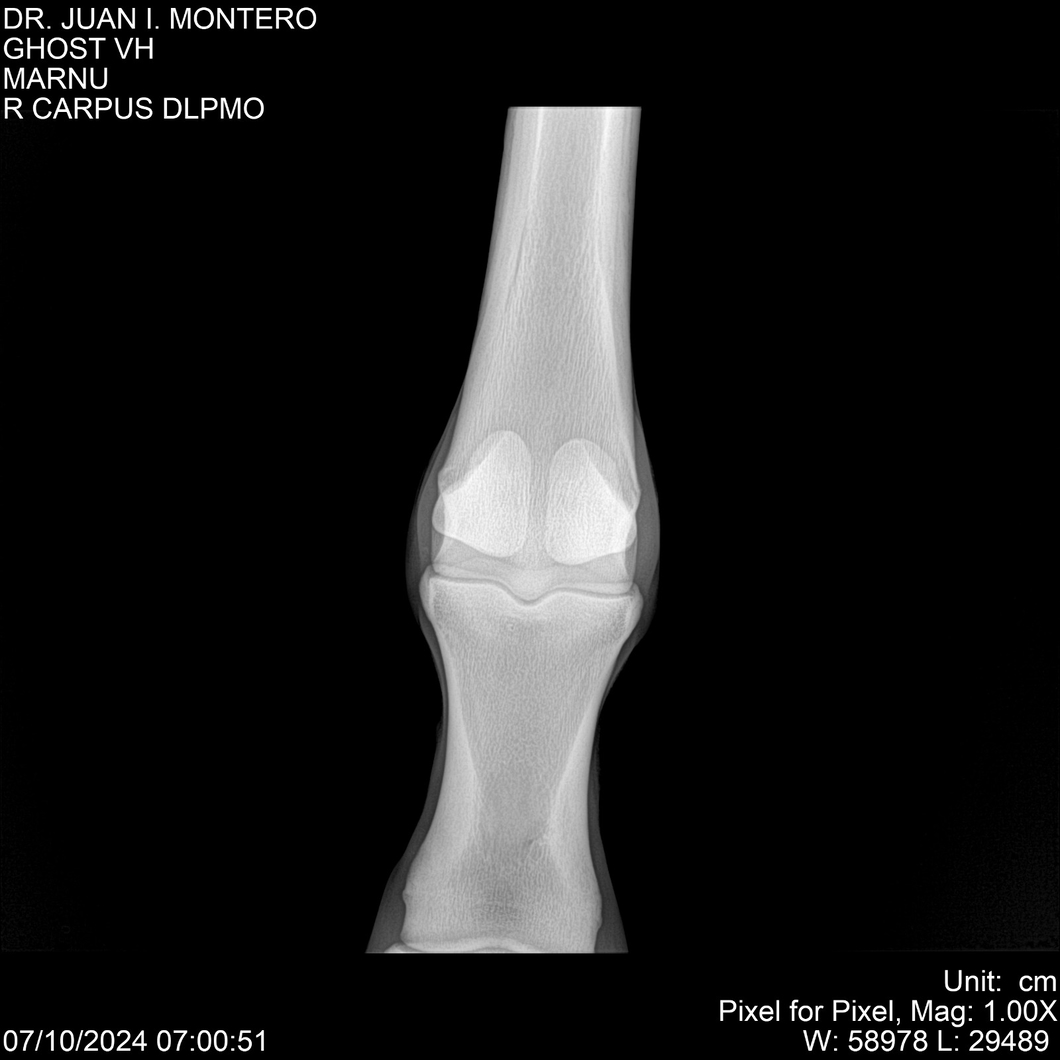

LOTE 15, GHOST VH 🔥 🔥 🔥 Lote Anterior Volver al remate Lote Siguiente Ficha Contacto Montevideo - Ficha del Lote Identificador: #282525 Categoría: Yeguarizos Montevideo - 69 Visualizaciones ClicData Contacto Empresa: Abelenda N. R., Walter Hugo Nombre*: Teléfono* : E-mail* : Mensaje Enviar Registrese gratis Este contenido Exclusivo está disponible sólo para usuarios registrados Ingresar